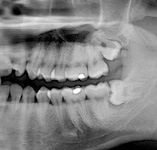

Zuby moudrosti (lidově „osmičky“) se zakládají v čelistech jako poslední zuby kolem 8. roku života a zpravidla prořezávají do dutiny ústní po 17. roce života. Proto velice často není místo pro jejich zařazení do správné polohy a zůstávají částečně nebo úplně skryté v kosti. Mohou být různě skloněné či zdeformované. Dále mohou nepříznivě působit i na sousední zuby či okolní měkké tkáně kolem čelistí a vyvolávat bolestivé záněty.

Jejich odstranění je někdy jednoduché, někdy obtížnější. Vždy je potřeba provést jejich odstranění v období, kdy jsou v klidu bez známek akutního zánětu (otok, bolest, teplota…).